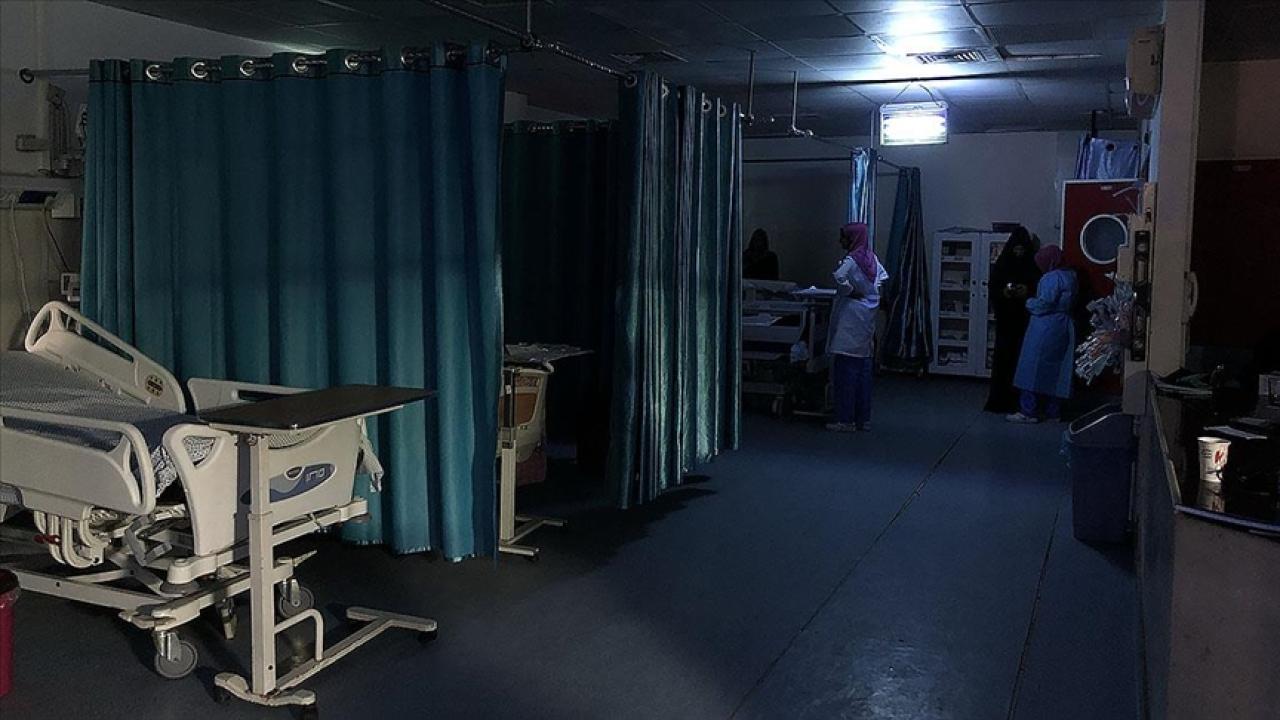

Bakan Koca: Vaka artışı 40 katına çıktı, hastane yükü 3 kat arttı

Şu dönem, günlük vaka sayısında Almanya, İtalya, Fransa gibi gelişmiş Avrupa ülkelerinde 100 binleri geçen vakaların görüldüğünü ifade eden Koca, “Bizde ise giderek artan bir vaka sayısı olduğunu görüyoruz. Vaka sayısının artışıyla birlikte hastane yükü aynı oranda artmıyor. Vaka sayısı artışı şu an günlük 40 katına kadar çıkmış durumda. Hastane yükü ise şu an 3 kat kadar arttı. O anlamda ciddi bir hastane yükümüzün olmadığını çok rahat söyleyebiliriz. Yoğun bakımlarda da bu artışların belirgin ve ciddi olmadığını görüyoruz. Artışın aynı oranda olmadığını rahatlıkla söyleyebiliriz.” diye konuştu.

Yeni yoğun bakımlar açılmasının söz konusu olup olmadığı sorusu üzerine Koca, “Hayır, şu an yenilerin açılması gibi bir durum yok. Panik havası yok ama biz bundan sonra tedbirlere devam ederek Kovid’le birlikte nasıl yaşamamız gerektiğini biliyoruz. Nerede maske takılması gerektiğini, nerede kendimizi korumamız gerektiğini artık hepimiz biliyoruz. Yeniden kapatma ve benzeri durumlar olmayacak. Aşımız var, ilacımız var, tedbirlere devam.” ifadesini kullandı.